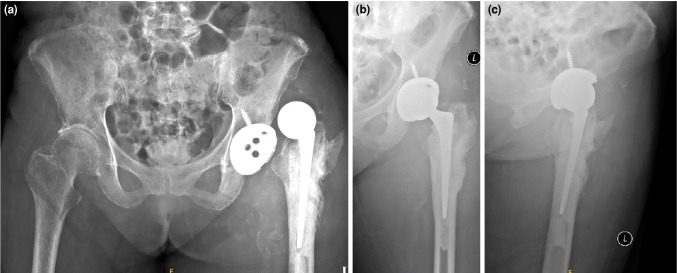

假体周围关节感染(PJI)仍然是全髋关节置换术(THA)后的一个具有挑战性的并发症,通常通过两阶段翻修来管理,这可能导致显著的发病率。在这篇文章中,我们提出一个罕见的病例肠炎沙门氏菌PJI,最初表现为假体髋关节脱位。术前使用血培养瓶进行髋关节抽吸可以早期识别细菌并指导靶向抗菌治疗。患者使用固定良好的定制关节间隔器(CUMARS)结构进行翻修THA,并使用靶向抗生素骨水泥。一年的随访表明感染成功根除,植入物固定稳定,功能预后良好。总之,该病例强调了诊断髋关节抽吸的重要性,并强调了CUMARS技术作为治疗由肠炎沙门氏菌等非典型生物引起的罕见PJIs的有效和持久解决方案的潜力。

Periprosthetic joint infection (PJI) remains a challenging complication following total hip arthroplasty (THA), commonly managed through a two-stage revision which can lead to significant morbidity. In this article, we present a rare case of Salmonella enteritidis PJI, initially presenting as prosthetic hip dislocation. Preoperative hip aspiration utilizing blood culture bottles enabled early identification of the organism and guided targeted antimicrobial therapy. The patient underwent revision THA using a well-fixed custom-made articulating spacer (CUMARS) construct, with targeted antibiotic-loaded bone cement. One-year follow-up demonstrated successful eradication of the infection, stable implant fixation, and good functional outcomes. In conclusion, this case underscores the importance of diagnostic hip aspiration and highlights the potential of the CUMARS technique as an effective and durable solution for managing rare PJIs caused by atypical organisms such as Salmonella enteritidis.